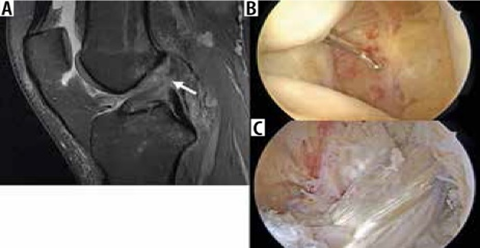

Hình 3. Hình ảnh cộng hưởng từ có trọng số mật độ proton sagital có sụn chêm bên dạng đĩa với tín hiệu tăng trong sụn.

Một lớp sụn chêm đã được chứng minh là có liên quan đến các vết rách của rễ sụn trung gian sừng sau; một nghiên cứu đã chứng minh rằng các vết nứt sụn xuất hiện ở gốc sau sụn trung gian trong 89% trường hợp, và sụn chêm bị rách trong 98% trường hợp (Hình 4)[9].

Bác sĩ phẫu thuật có thể thực hiện cắt sụn một phần, cắt bỏ sụn chêm hoặc sửa chữa trực tiếp các vết rách sụn chêm. Tiêu chuẩn đánh giá rách sụn chêm sau phẫu thuật trở nên khó áp dụng vì hình dạng sau phẫu thuật của sụn chêm trùng với tiêu chuẩn chẩn đoán rách sụn chêm. Khi phẫu thuật cắt một phần khum, tín hiệu bất thường ban đầu là nội tạng bên trong sụn chêm có thể được chuyển thành tín hiệu chạm vào bề mặt trên hoặc bề mặt dưới. Mô hạt từ vết rách sụn chêm đang lành cũng có thể có các đặc điểm tín hiệu tương tự như vết rách. Do đó, việc chẩn đoán vết rách sụn chêm còn sót lại hoặc mới trong các trường hợp sau phẫu thuật dựa vào sự hiện diện của các mảnh sụn bị di lệch hoặc các nang thông số, hoặc sự hiện diện của cường độ tín hiệu dịch/gadolinium kéo dài vào sụn chêm (Hình 8)[8].

Hình 9. Rách sụn chêm và mô hạt đang lành sau mổ. A là hình ảnh T1 xóa mỡ sau khi tiêm thuốc tương phản trong khớp với tín hiệu tuyến tính sụn chêm bên có giá trị trung gian về cường độ tín hiệu (mũi tên trắng), so với chất tương phản sáng được tiêm vào không gian khớp (mũi tên mở), có thể đại diện cho mô hạt trong sụn chêm bên đã được phẫu thuật sửa chữa trước đó. B là hình ảnh T1 xóa mỡ sau khi tiêm thuốc tương phản nội khớp cho thấy khiếm khuyết cường độ sáng tương phản (mũi tên đen) ở sụn chêm giữa, biểu thị vết rách xuyên tâm.